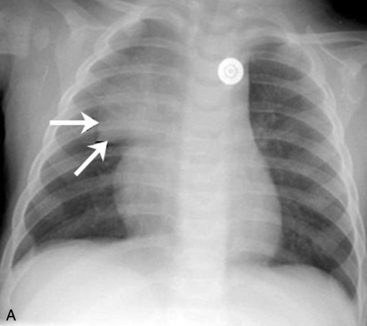

If the film is obtained during expiration, the heart will appear larger and less well defined. The lung fields will appear to be hazier and the pulmonary vascular markings more prominent. Hypoinflation of the lung fields can lead to misinterpretation of the images and misdiagnosis of a basilar pneumonia or cardiomegaly. Furthermore, if maximal inspiration is not present, the lungs can appear more congested and the trachea will appear to buckle to the right.21,24 Figure 10-2 illustrates these differences with two views obtained from a normal child during inspiration and expiration.

image

Fig. 10-2 Inspiratory and expiratory chest radiograph. Normal chest films obtained from the same child during inspiration and expiration. A, Inspiratory phase. Nine ribs can be counted above the diaphragm, indicating good inspiration. Alignment is good (note similarity of clavicles). Penetration of film is good (all vertebral bodies are visible; some pulmonary vascular markings can be seen). Intercostal spaces are equal; both sides of the diaphragm are visible. The mediastinum and trachea are straight (arrows). Heart borders are sharply defined, and heart size is normal. Pulmonary vascular markings are visible in the proximal two thirds of lung fields (normal). B, Expiratory phase. Only eight ribs are visible above the diaphragm (see numbers on ribs), indicating inadequate lung expansion. Alignment is good. Penetration of film is good. Intercostal spaces are narrow because expiration is occurring. Both sides of the diaphragm are hazy, and the left hemidiaphragm is not readily identifiable. The mediastinum appears widened, and the trachea seems to buckle to the right (arrows). Heart appears much larger than in A, and the heart borders are obliterated, but this is caused by expiration and reduction in apparent lung volume. Silhouette sign appears to be present, cardiothoracic size calculated from this view would be large, and pulmonary vascular markings appear prominent, but these are all artifacts caused by expiration.

(Courtesy H. Rex Gardner, Rush Presbyterian Saint Luke’s Hospital, Chicago, IL.)